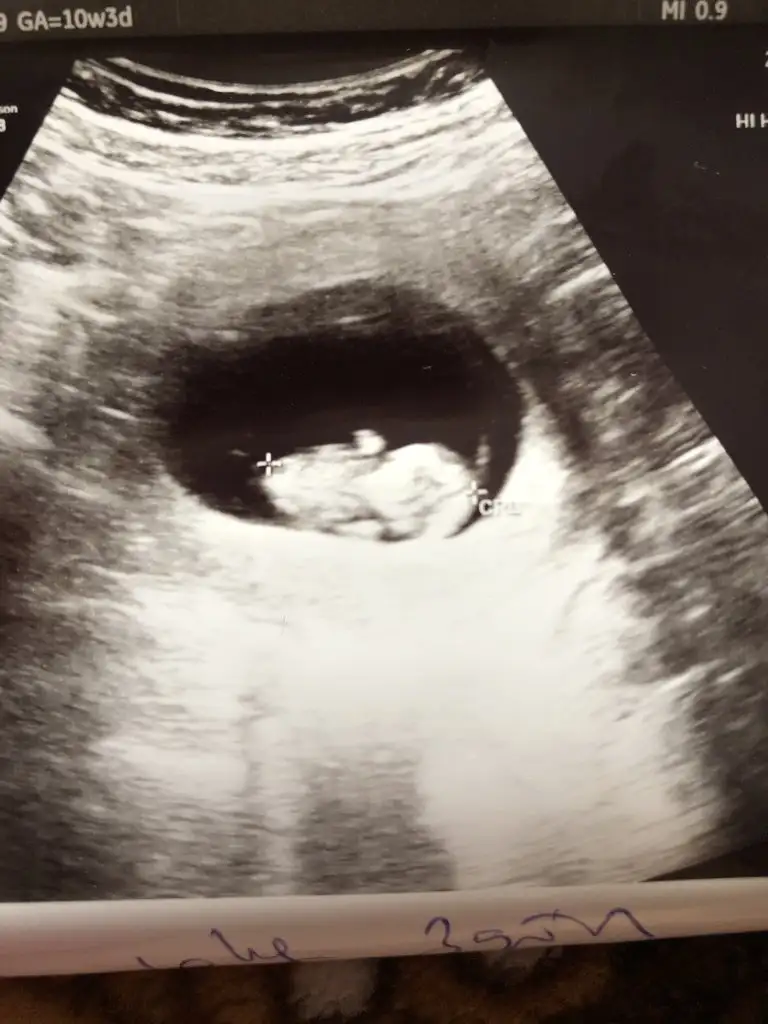

Ayy banada bakın 😀 10+3 karından ultrason

• image.webp

image.webp

31,2 KB · Görüntüleme: 84

Ultrsonea kıza mı benzıor inşallah kızdır:)

İnsallah Çin takvimi doğru çıkar kızım olur